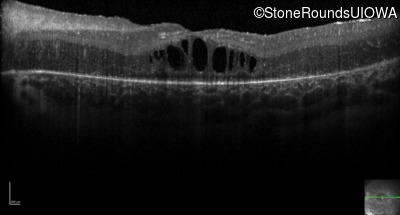

Optical Coherence Tomography - Right - 20/200 -2

Exemplar / OCT Stack

OCT Stack